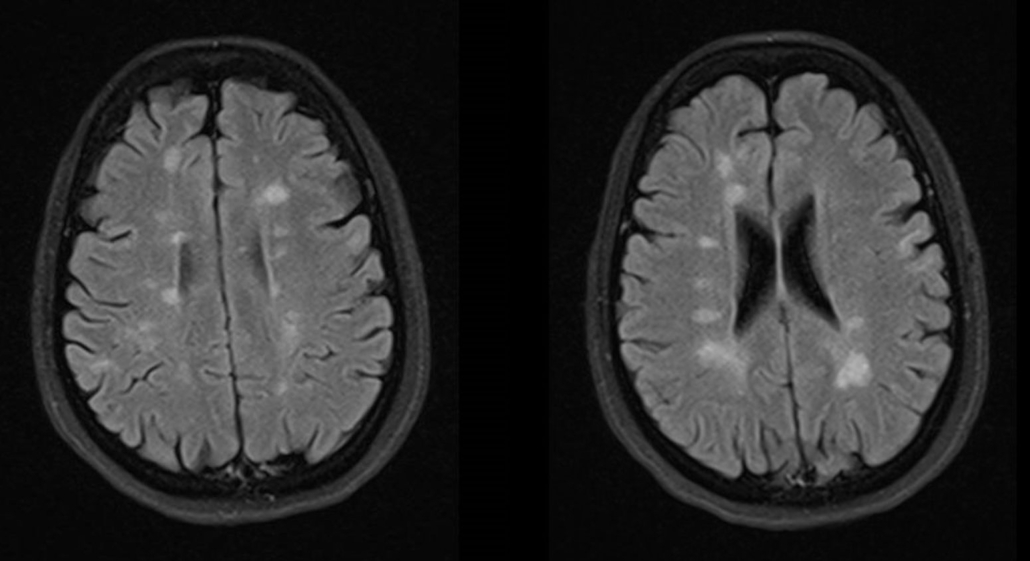

La más conocida es la esclerosis múltiple. Afecta más habitualmente a adultos jóvenes, siendo los síntomas visuales, motores o sensitivos los más frecuentes. Lo primordial es diagnosticarla cuando da los primeros síntomas, para no demorar un tratamiento, habitualmente de administración hospitalaria, que hoy por hoy tiene múltiples posiblidades y alcanza una gran eficacia, evitando así la progresión de la enfermedad y la acumulación de secuelas.

En fases más avanzadas de la enfermedad, que observamos cuando el diagnóstico ha sido tardío o en los cada vez menos frecuentes casos con mala respuesta a las líneas terapéuticas existentes, pueden aparecer otros síntomas como el dolor, la espasticidad o la disfunción esfinteriana, que también tienen tratamientos específicos para mejorar la calidad de vida.